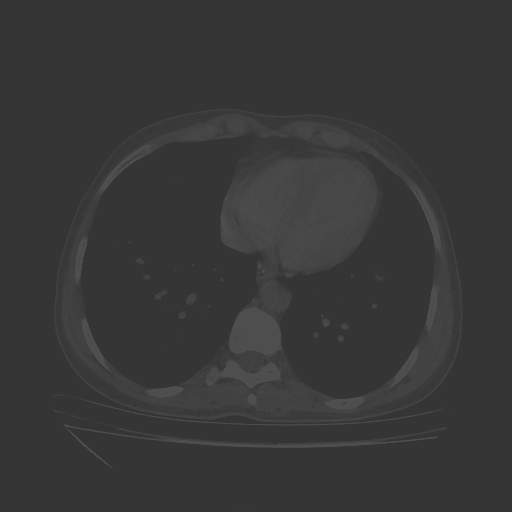

Original NATIVE CT scan (input)

No window - Raw intensity values

Lung window (WL -600, WW 1500 β†’ Low βˆ’1350, High +150)

Mediastinum window (WL 40, WW 400 β†’ Low βˆ’160, High +240)